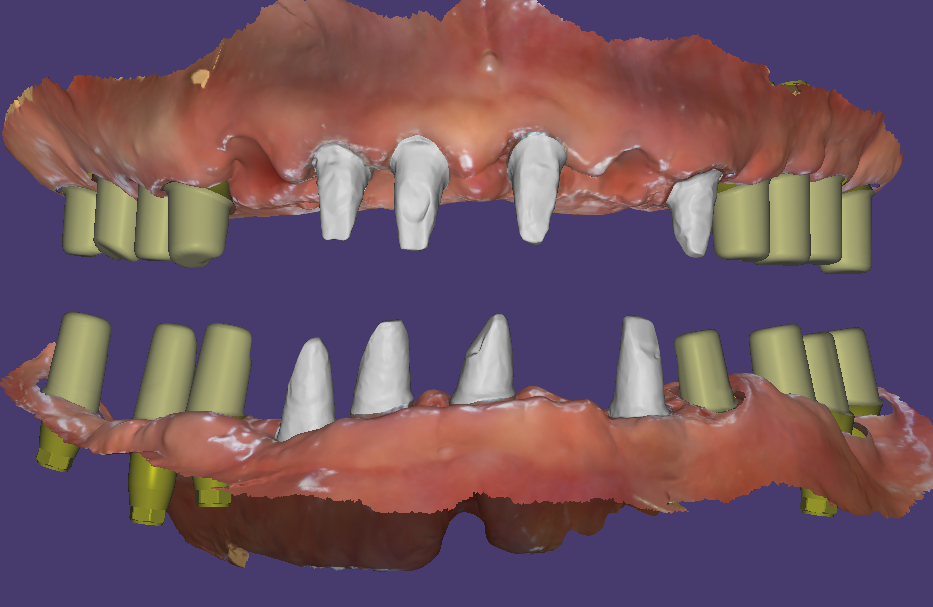

흔들리는 모든 치아를 발치하고 염증을 제거한 다음 즉시식립을 시도했습니다. 위에는 12개, 아래는 11개의 임플란트를 식립했어요.

식립한 임플란트에 지대주를 연결해서 수술당일 임시치아를 만들었습니다. 임시치아를 디자인할 때 고경을 높여서 붕괴된 교합을 수정해 주었습니다.

3개월후 스캔바디 스캔해서 최종보철 디자인

이 분은 교합상태는 좋지 않았지만 뼈상태는 양호하신 편이라 임플란트의 초기고정이 좋아 3개월 후에 2차를 진행했습니다.

스캔바디를 끼우고 스캔을 하면 임플란트의 위치를 디자인프로그램에서 확인할 수 있어요. 거기에 맞게 맞춤지대주를 디자인하고 그 위에 지르코니아 보철디자인까지 한꺼번에 진행이 됩니다.